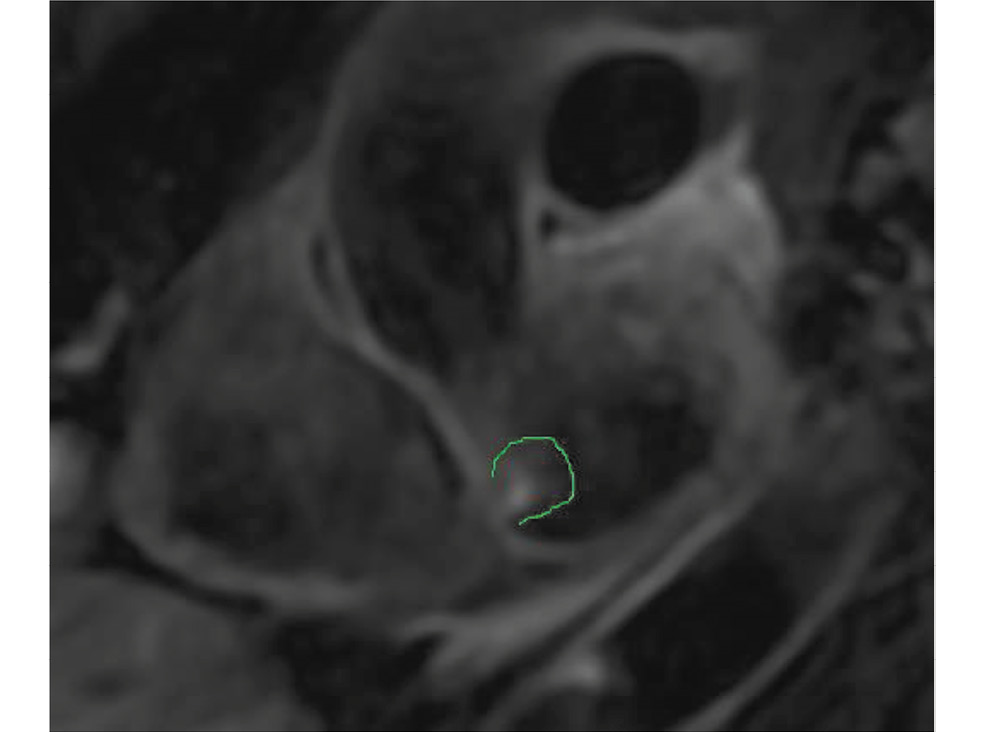

ЛЖ не увеличен. Имеет место его концентрическое ремоделирование. ЛП умеренно увеличено. В полости ЛП, в области срединной части межпредсердной перегородки (МПП) лоцируется образование неправильной формы размером около 10 мм, рыхлое, с мелкими флотирующими фрагментами, фиксированное к МПП (тромб? миксома?) (рис. 1). Аорта не расширена. Клапан трёхполулунный, не изменён. Нарушений кровотока не установлено. Створки митрального клапана не изменены. Имеется регургитация 1-й ст. Правые отделы сердца не расширены. Глобальная сократимость правого желудочка не снижена. Пульмональный и трёхстворчатый клапаны обычные. Лёгочный ствол не расширен. Нижняя полая вена не расширена, спадается более 50%. Расчётное систолическое давление в лёгочной артерии — 30 мм рт.ст. Межпредсердная перегородка тонкая, патологического сброса через неё не найдено. Избытка в полости перикарда нет.

Рис. 1. Миксома левого предсердия по данным эхографического исследования (обведено красным контуром). / Fig. 1. Myxoma of the left atrium according to the data of the echographic study (circled in red).